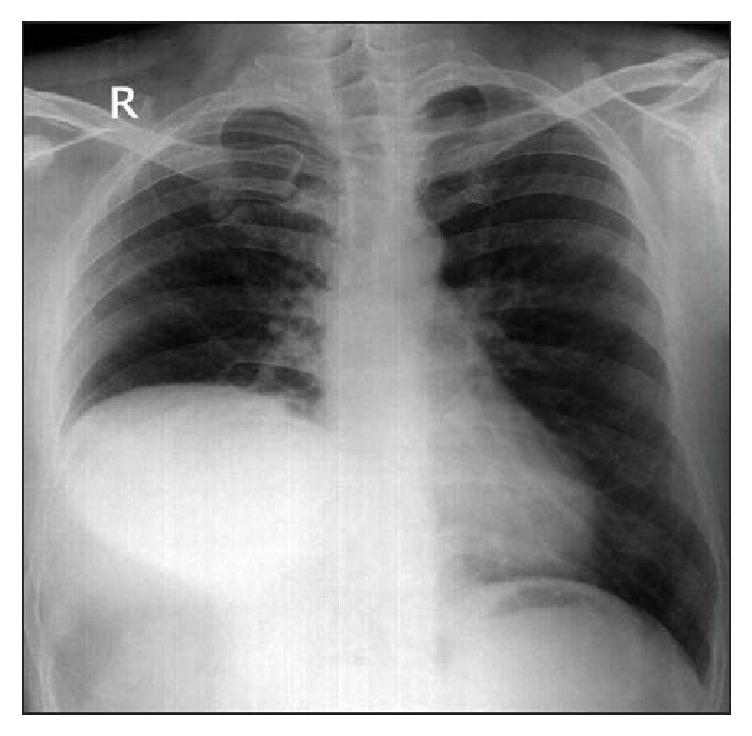

伴有半膈麻痹的有症状卵圆孔未闭

Symptomatic Patent Foramen Ovale with Hemidiaphragm Paralysis.

Dyspnea accounts for more than one-fourth of the hospital admissions from Emergency Department. Chronic conditions such as Chronic Obstructive Pulmonary Disease, Congestive Heart Failure, and Asthma are being common etiologies. Less common etiologies include conditions such as valvular heart disease, pulmonary embolism, and right-to-left shunt (RLS) from patent foramen ovale (PFO). PFO is present in estimated 20-30% of the population, mostly a benign condition. RLS via PFO usually occurs when right atrium pressure exceeds left atrium pressure. RLS can also occur in absence of higher right atrium pressure. We report one such case that highlights the importance of high clinical suspicion, thorough evaluation, and percutaneous closure of the PFO leading to significant improvement in the symptoms.

摘要

呼吸困难占急诊科住院患者的四分之一以上。慢性阻塞性肺疾病、充血性心力衰竭和哮喘等慢性疾病是常见病因。较少见的病因包括瓣膜性心脏病、肺栓塞以及卵圆孔未闭(PFO)导致的右向左分流(RLS)。估计20%-30%的人群存在PFO,大多为良性情况。通过PFO的RLS通常在右心房压力超过左心房压力时发生。在没有较高右心房压力的情况下也可能发生RLS。我们报告了这样一个病例,强调了高度临床怀疑、全面评估以及经皮闭合PFO对显著改善症状的重要性。